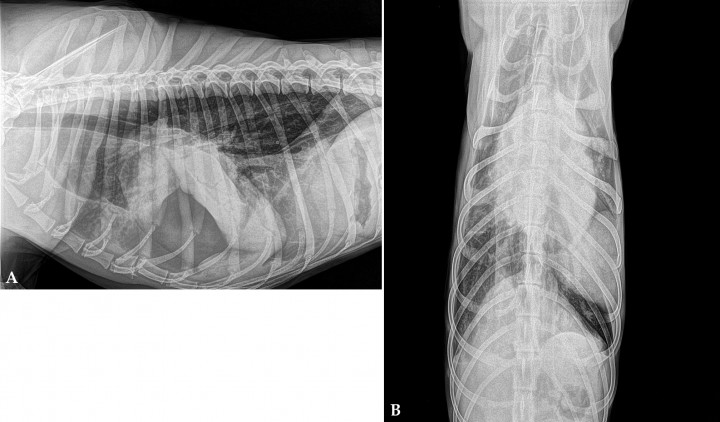

Se presenta un Galgo Español, hembra ovariohisterectomizada, de 3 años de edad y 20 kg de peso con un cuadro agudo de disnea inspiratoria con respiración superficial. A la auscultación se evidencia taquicardia y disminución de los sonidos broncovesiculares en hemitórax izquierdo en las zonas media y ventral. El hemograma y la bioquímica sanguínea no muestran hallazgos significativos. Se realizan radiografías torácicas bajo sedación en proyecciones lateral derecha y ventrodorsal (Fig. 1). Mediante drenaje pleural se obtiene un líquido de aspecto lechoso compatible con quilo.

<p>Radiografías de cavidad torácica de un Galgo de 3 años de edad. (<strong>A</strong>) Radiografía lateral derecha. (<strong>B</strong>) Radiografía ventrodorsal.</p>

Radiografías de cavidad torácica de un Galgo de 3 años de edad. (A) Radiografía lateral derecha. (B) Radiografía ventrodorsal.